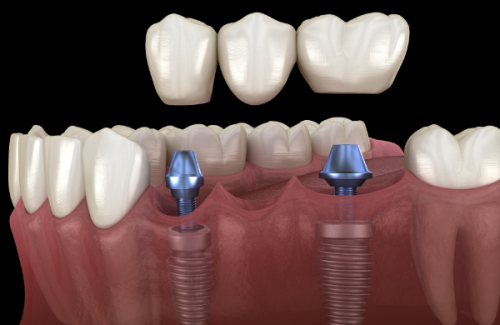

此外,技术升级带来的成功概率提升,避免了因种植失败导致的二次治疗费用。传统模式中,患者可能因医生经验不足或设备落后承担额外风险,而中诺口腔通过标准化流程和新型设备,将种植牙的成功概率维持在较优质水平,从长远看反而更省钱。中诺口腔应用的即刻负重技术(如“立得用”),实现“当天种牙当天用”,将传统种植3 - 6个月的愈合周期压缩至24小时内。